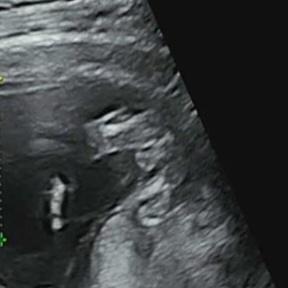

14주사진인데 이거 고추인가요...??

교수님께서 확대해주시긴 했는데 확답을 안 해주시고 16주에 확정해준다고 하셨거든요 혹시 이게 고추인가요???